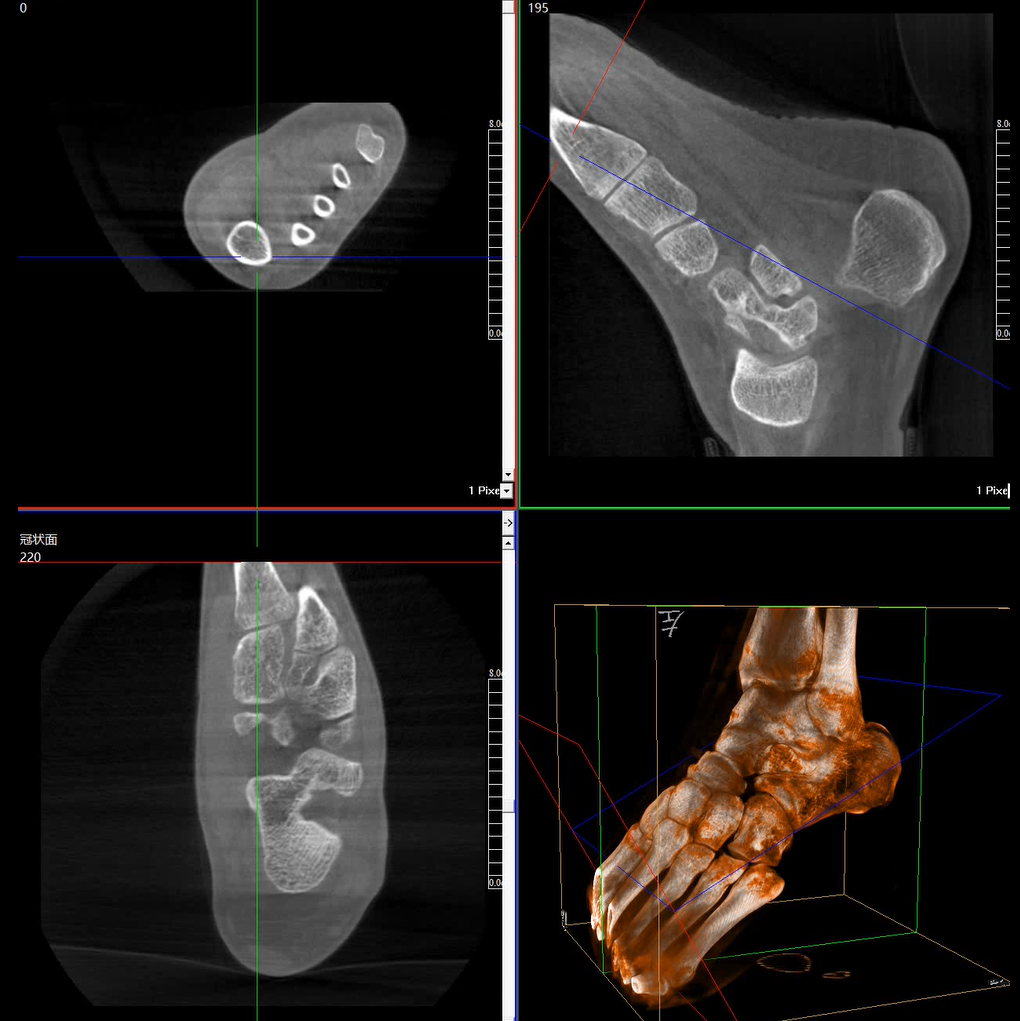

術(shù)中三維成像和橫斷面圖像提供多角度的手術(shù)診斷信息,輔助醫(yī)生進(jìn)行術(shù)中評估判斷,諸如骨折復(fù)位情況和內(nèi)植入螺釘?shù)某叽绾臀恢?,輔助手術(shù)更好地完成。

提供更大的術(shù)中三維成像視野,采集更多圖像信息,可一次拍全全段頸椎、全段腰椎、七節(jié)胸椎、雙側(cè)骶髂關(guān)節(jié)、股骨頭及單側(cè)盆骨。

在C臂掃描過程中,始終保持拍攝主體處于射線束的中心,避免了序列圖像采集過程中的橫縱方向運動,減少相對運動造成的運動偽影。

平板垂直升降運動 便于術(shù)中微調(diào)平板與拍攝主體的距離,更加貼近病灶體,成像范圍更大,圖像更清晰。